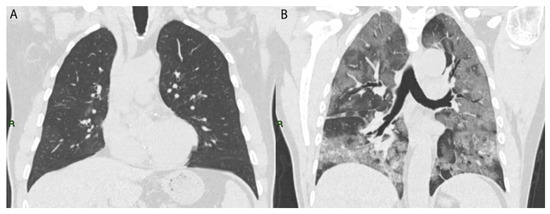

Bilaterality of pulmonary disease was found in 100% of the evaluated patients.

The typical patterns observed were: GGOs (defined as hazy increased opacities of the lung with the preservation of bronchovascular margins), consolidation (a homogeneous increase in pulmonary parenchymal attenuation that obscures the margins of vessels and airway walls), GGOs plus consolidations (consolidations superimposed on a background of GGOs), GGOs plus subpleural bands (subpleural bands defined as thin curvilinear opacities with 1–3 mm thickness, lying less than 1 cm from and parallel to the pleural surface) and parenchymal bands (defined as linear opacities, usually 1–3 mm thick and up to 5 cm long that usually extend to the visceral pleura) [19] (Figure 2).

Pleural effusion, which is an unusual manifestation of COVID-19 disease, was more present in the very early stages of the disease, in particular during the first wave (first wave: 41.4%; second wave: 20.4%; third wave: 32.8%; fourth wave: 23.9%) (Figure 2D; percentages reported in Figure 3, Figure S1 and Table S2).

Figure 2. Axial images of different evaluated patterns of COVID-19 (each marked with arrow keys): (A) bilateral ground glass (GGOs); (B) consolidation; (C) subpleural bands; (D) pleural effusion.